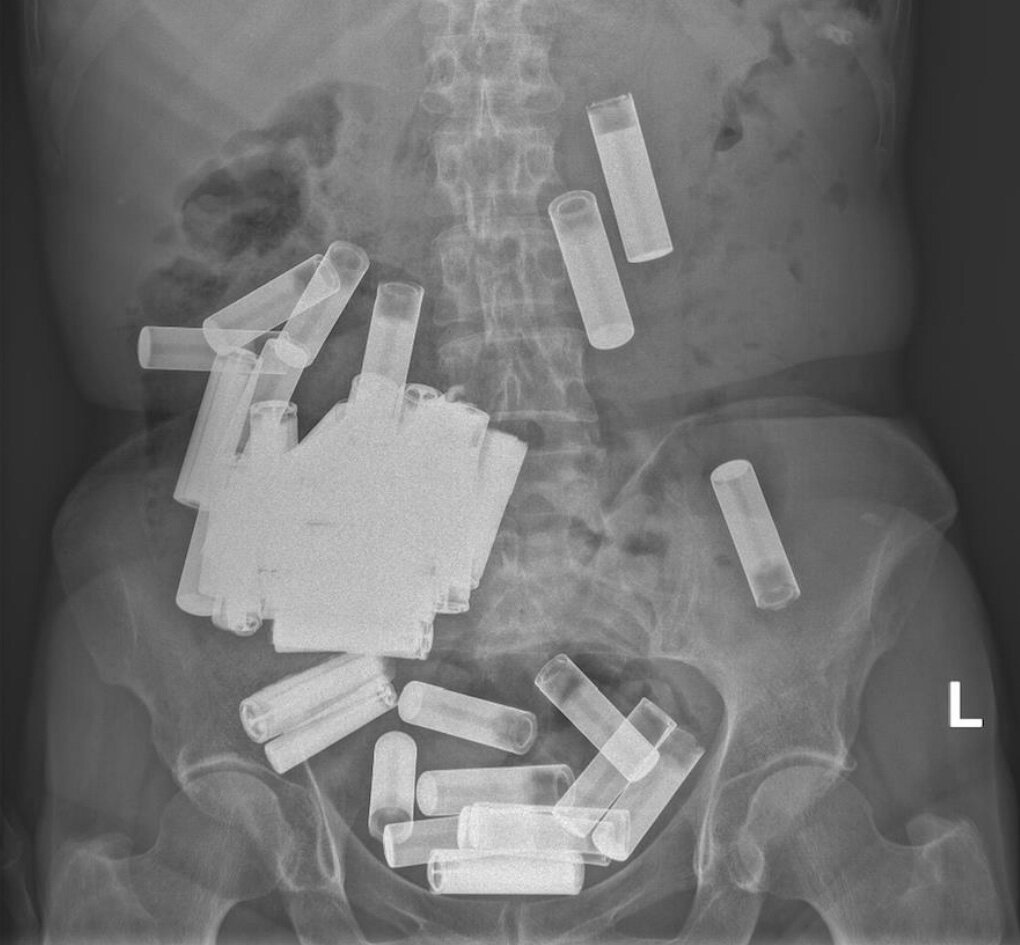

این زن ۶۶ ساله بر اساس گزارشی «ژورنال پزشکی ایرلند» پس بلعیدن «شمار نامعلومی» باتری قلمی در بیمارستان دانشگاه سنت وینسنت در شهر دوبلین تحت درمان قرار گرفت. رادیوگرافی اشعه ایکس مجموعهای از باتریها را در شکم او نشان داد، گرچه خوشبختانه هیچکدام از این باتریها ظاهرا باعث انسداد مجرای گوارشی او نشده بود و هیچکدام از باتریها هم نشانههای آسیب ساختاری را نشان نمیداد.

برای خارج کردن بقیه باتریها که در کولون یا روده بزرگ بیمار گیر کرده بودند، آنها با فشار ملایم دست آنها را به سوی راستروده بیمار راندند و از مقعد خارجشان کردند- به این ترتیب شمار کل باتریهای بلعیدهشده به ۵۵ رسید. اسکن اشعه ایکس نهایی ثابت کرد که دیگر باتری در دستگاه گوارش زن وجود ندارد و او بدون عارضه بهبود یافت.